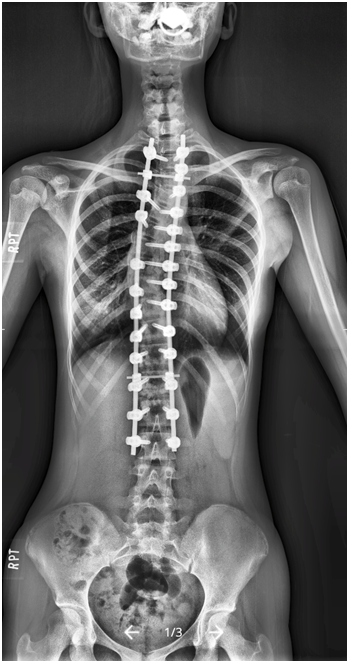

術前50度 → 術後10度